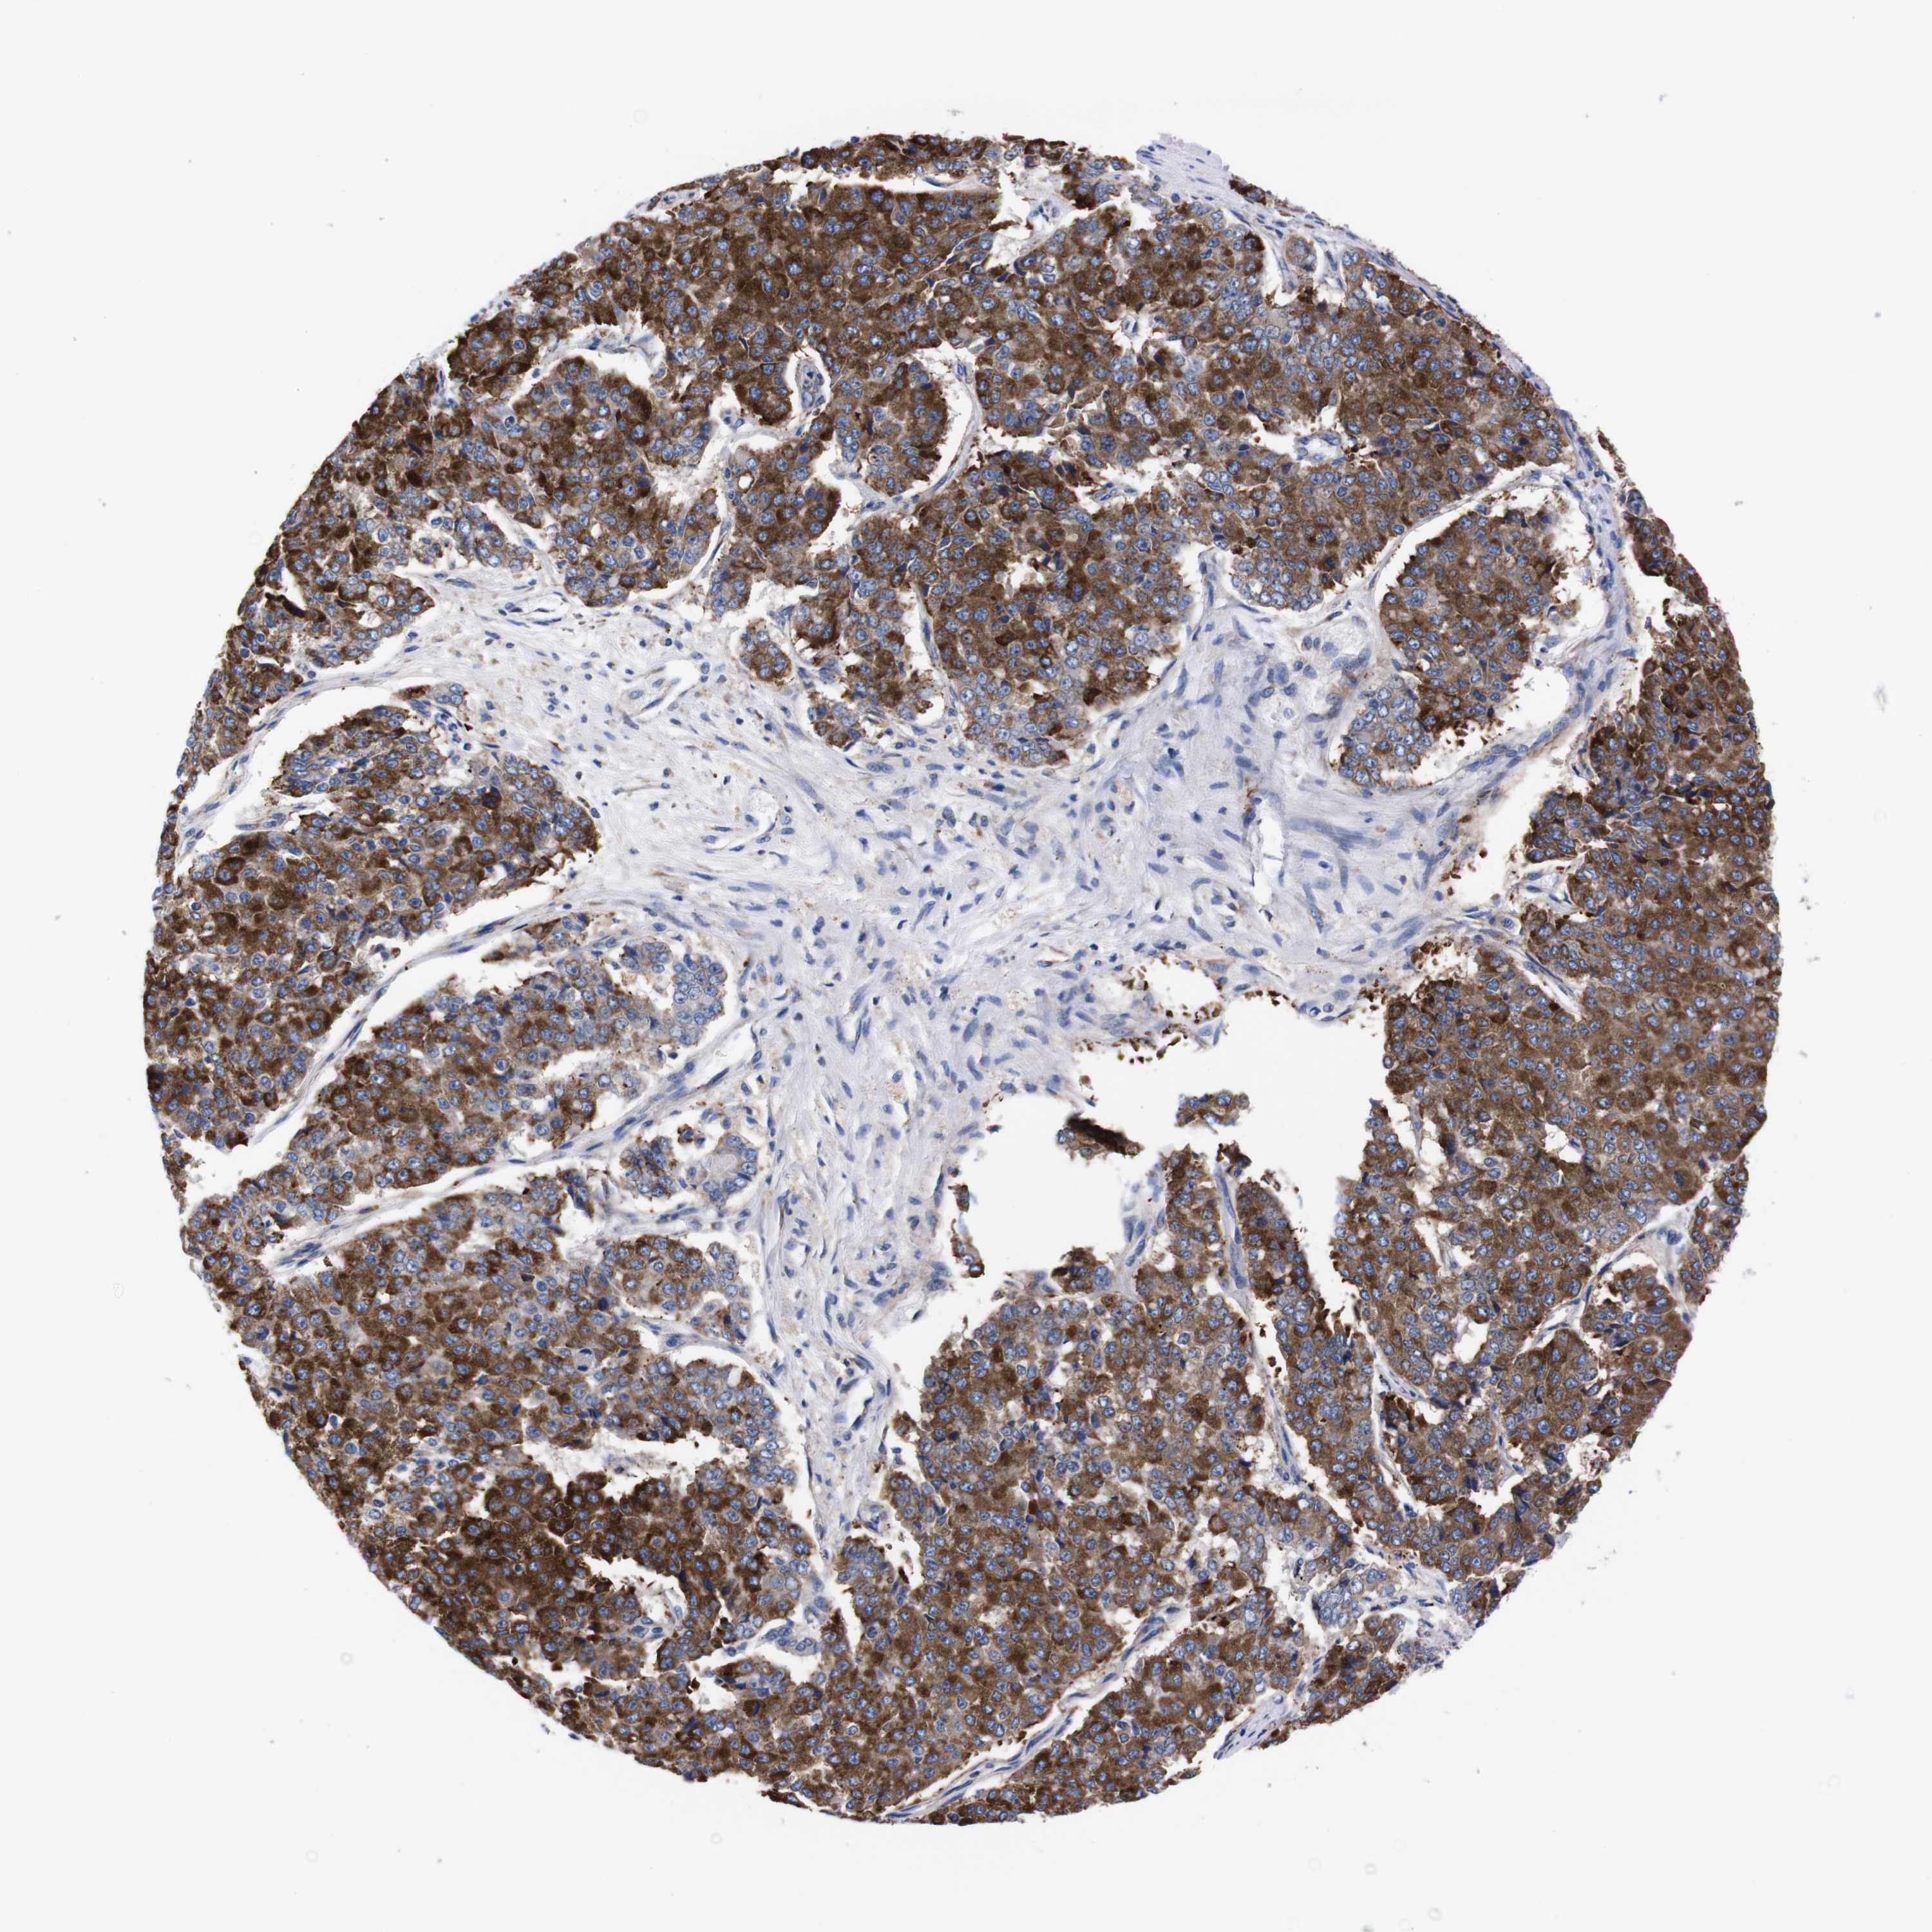

PANCREATIC CANCER - Protein expressioni

A mouse-over function shows sample information and annotation data. Click on an image to view it in a full screen mode. Samples can be filtered based on level of antibody staining by selecting one or several of the following categories: high, medium, low and not detected. The assay and annotation is described here.

Note that samples used for immunohistochemistry by the Human Protein Atlas do not correspond to samples in the TCGA dataset.

Antibody stainingi

Antibody staining in the annotated cell types in the current human tissue is reported as not detected, low, medium, or high, based on conventional immunohistochemistry profiling in selected tissues. This score is based on the combination of the staining intensity and fraction of stained cells.

Each image is clickable and will lead to virtual microscopy that enables deeper exploration of all samples and also displays staining intensity scores, fraction scores and subcellular localization as well as patient and tissue information for each sample.

Antibody HPA013994

Antibody HPA013995

Adenocarcinoma, NOS